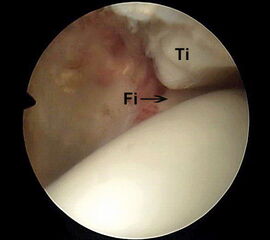

Abbildung 6 und 7, Video 2

Typischer Befund eines fibrotischen Faszikels (*), das zu einem Impingement am rechten lateralen Talus führt. Nach der Resektion des Faszikels ist der Blick auf das anterolaterale Gelenkeck zwischen der Tibia (Ti) und der Fibula (Fi) möglich.

Bei der intraoperativen Palpation mit dem Tasthaken zeigt sich die straffe Spannung des Faszikels und das mechanische Impingement an der lateralen Talusschulter. Oftmals finden sind entzündlich veränderte Synoviaanteile am Faszikel oder auch Schliffspuren am Knorpel der Taluskante.